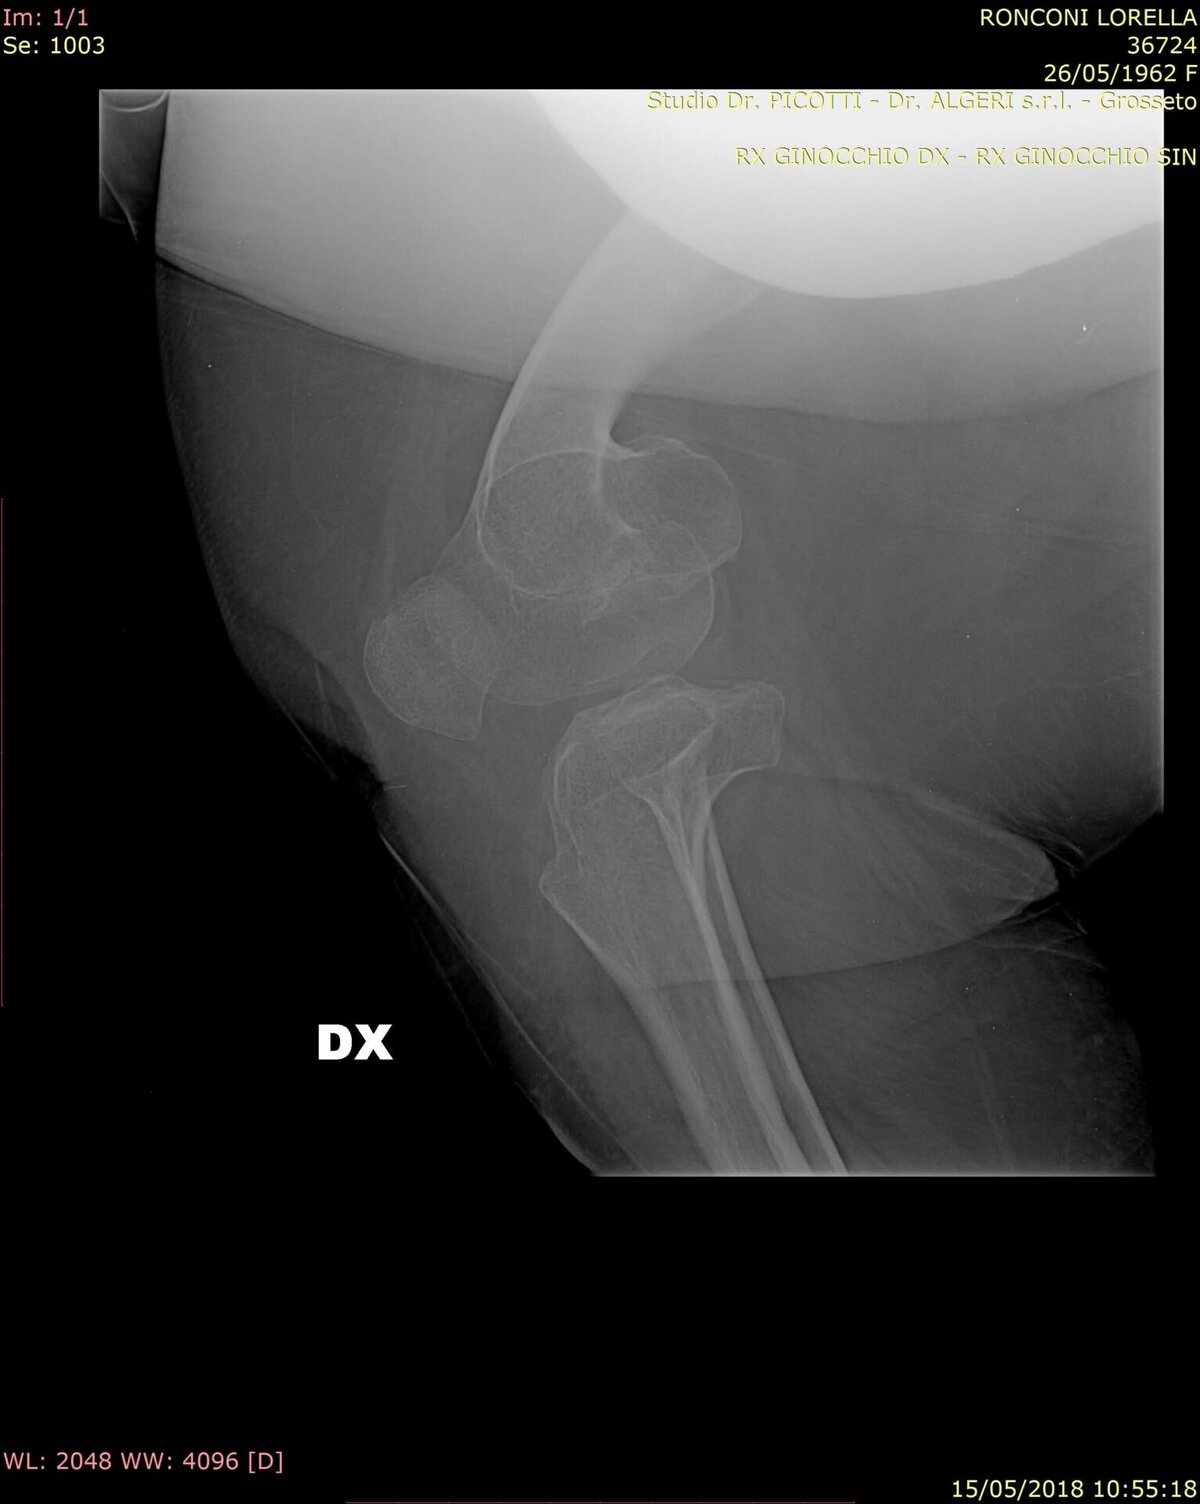

La diagnosi di pseudoacondroplasia si basa sull’insieme di segni clinici, reperti radiologici caratteristici e su un’accurata anamnesi del paziente. In particolare, gli esami radiografici evidenziano anomalie dei centri di accrescimento delle ossa (epifisi) e altre alterazioni scheletriche tipiche della patologia.

Tecniche di imaging più avanzate, come la risonanza magnetica (RM) e la tomografia computerizzata (TC), possono essere utilizzate nel corso della vita per valutare lo stato dello scheletro, in particolare in preparazione a interventi chirurgici finalizzati alla correzione delle deformità.

• deformità delle ginocchia, come il genu varo (ginocchia rivolte verso l’esterno) o il genu valgo (ginocchia rivolte verso l’interno);

Paradossalmente, mentre molte articolazioni presentano un’eccessiva mobilità, i gomiti possono mostrare una limitazione del movimento, creando ulteriori difficoltà funzionali. La lassità delle articolazioni del ginocchio contribuisce nel tempo allo sviluppo di deformità degli arti inferiori, come il genu varo (ginocchia rivolte verso l’esterno) o il genu valgo (ginocchia rivolte verso l’interno).